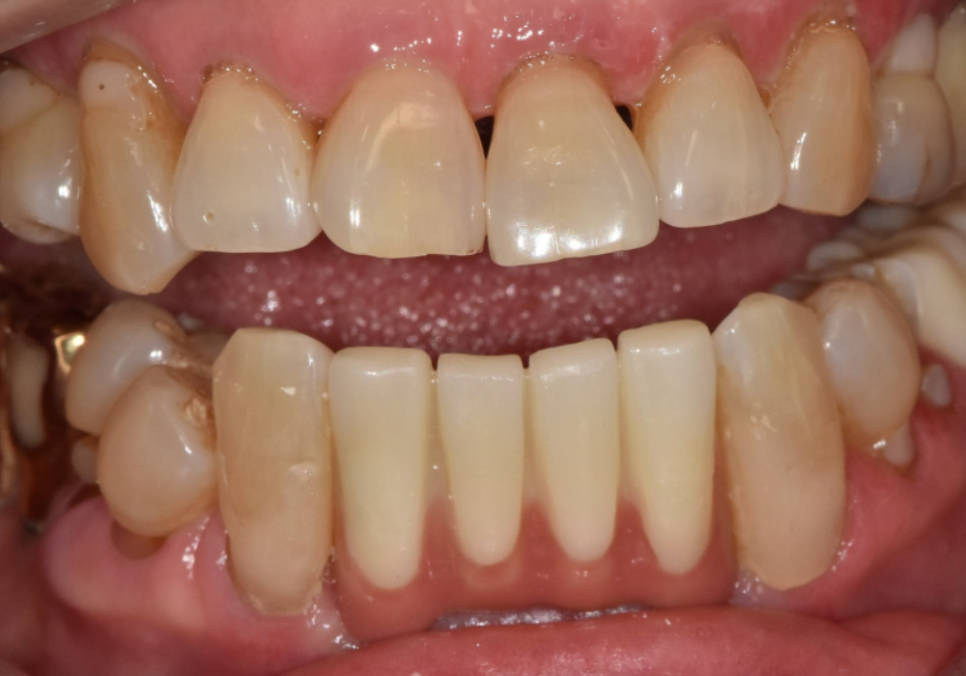

오랜 염증으로 잇몸뼈가 많이 내려가 있는 상태라,

일반적인 보철물을 올리면

치아가 비정상적으로 길어 보여

인상이 어색해질 우려가 컸는데요~

치아가 길어지지 않게

핑크 포세린(잇몸 색 도자기)으로

잇몸을 재현하여

260116

치아 길이가 짧아 보이도록

제작했습니다.

잇몸뼈가 많이 소실된 상황이었지만,

치아의 비율을 세심하게 조정한 덕분에 어색함 없이 아주 자연스러운 결과가 나왔습니다.^^

251022 (전) 260116(후)